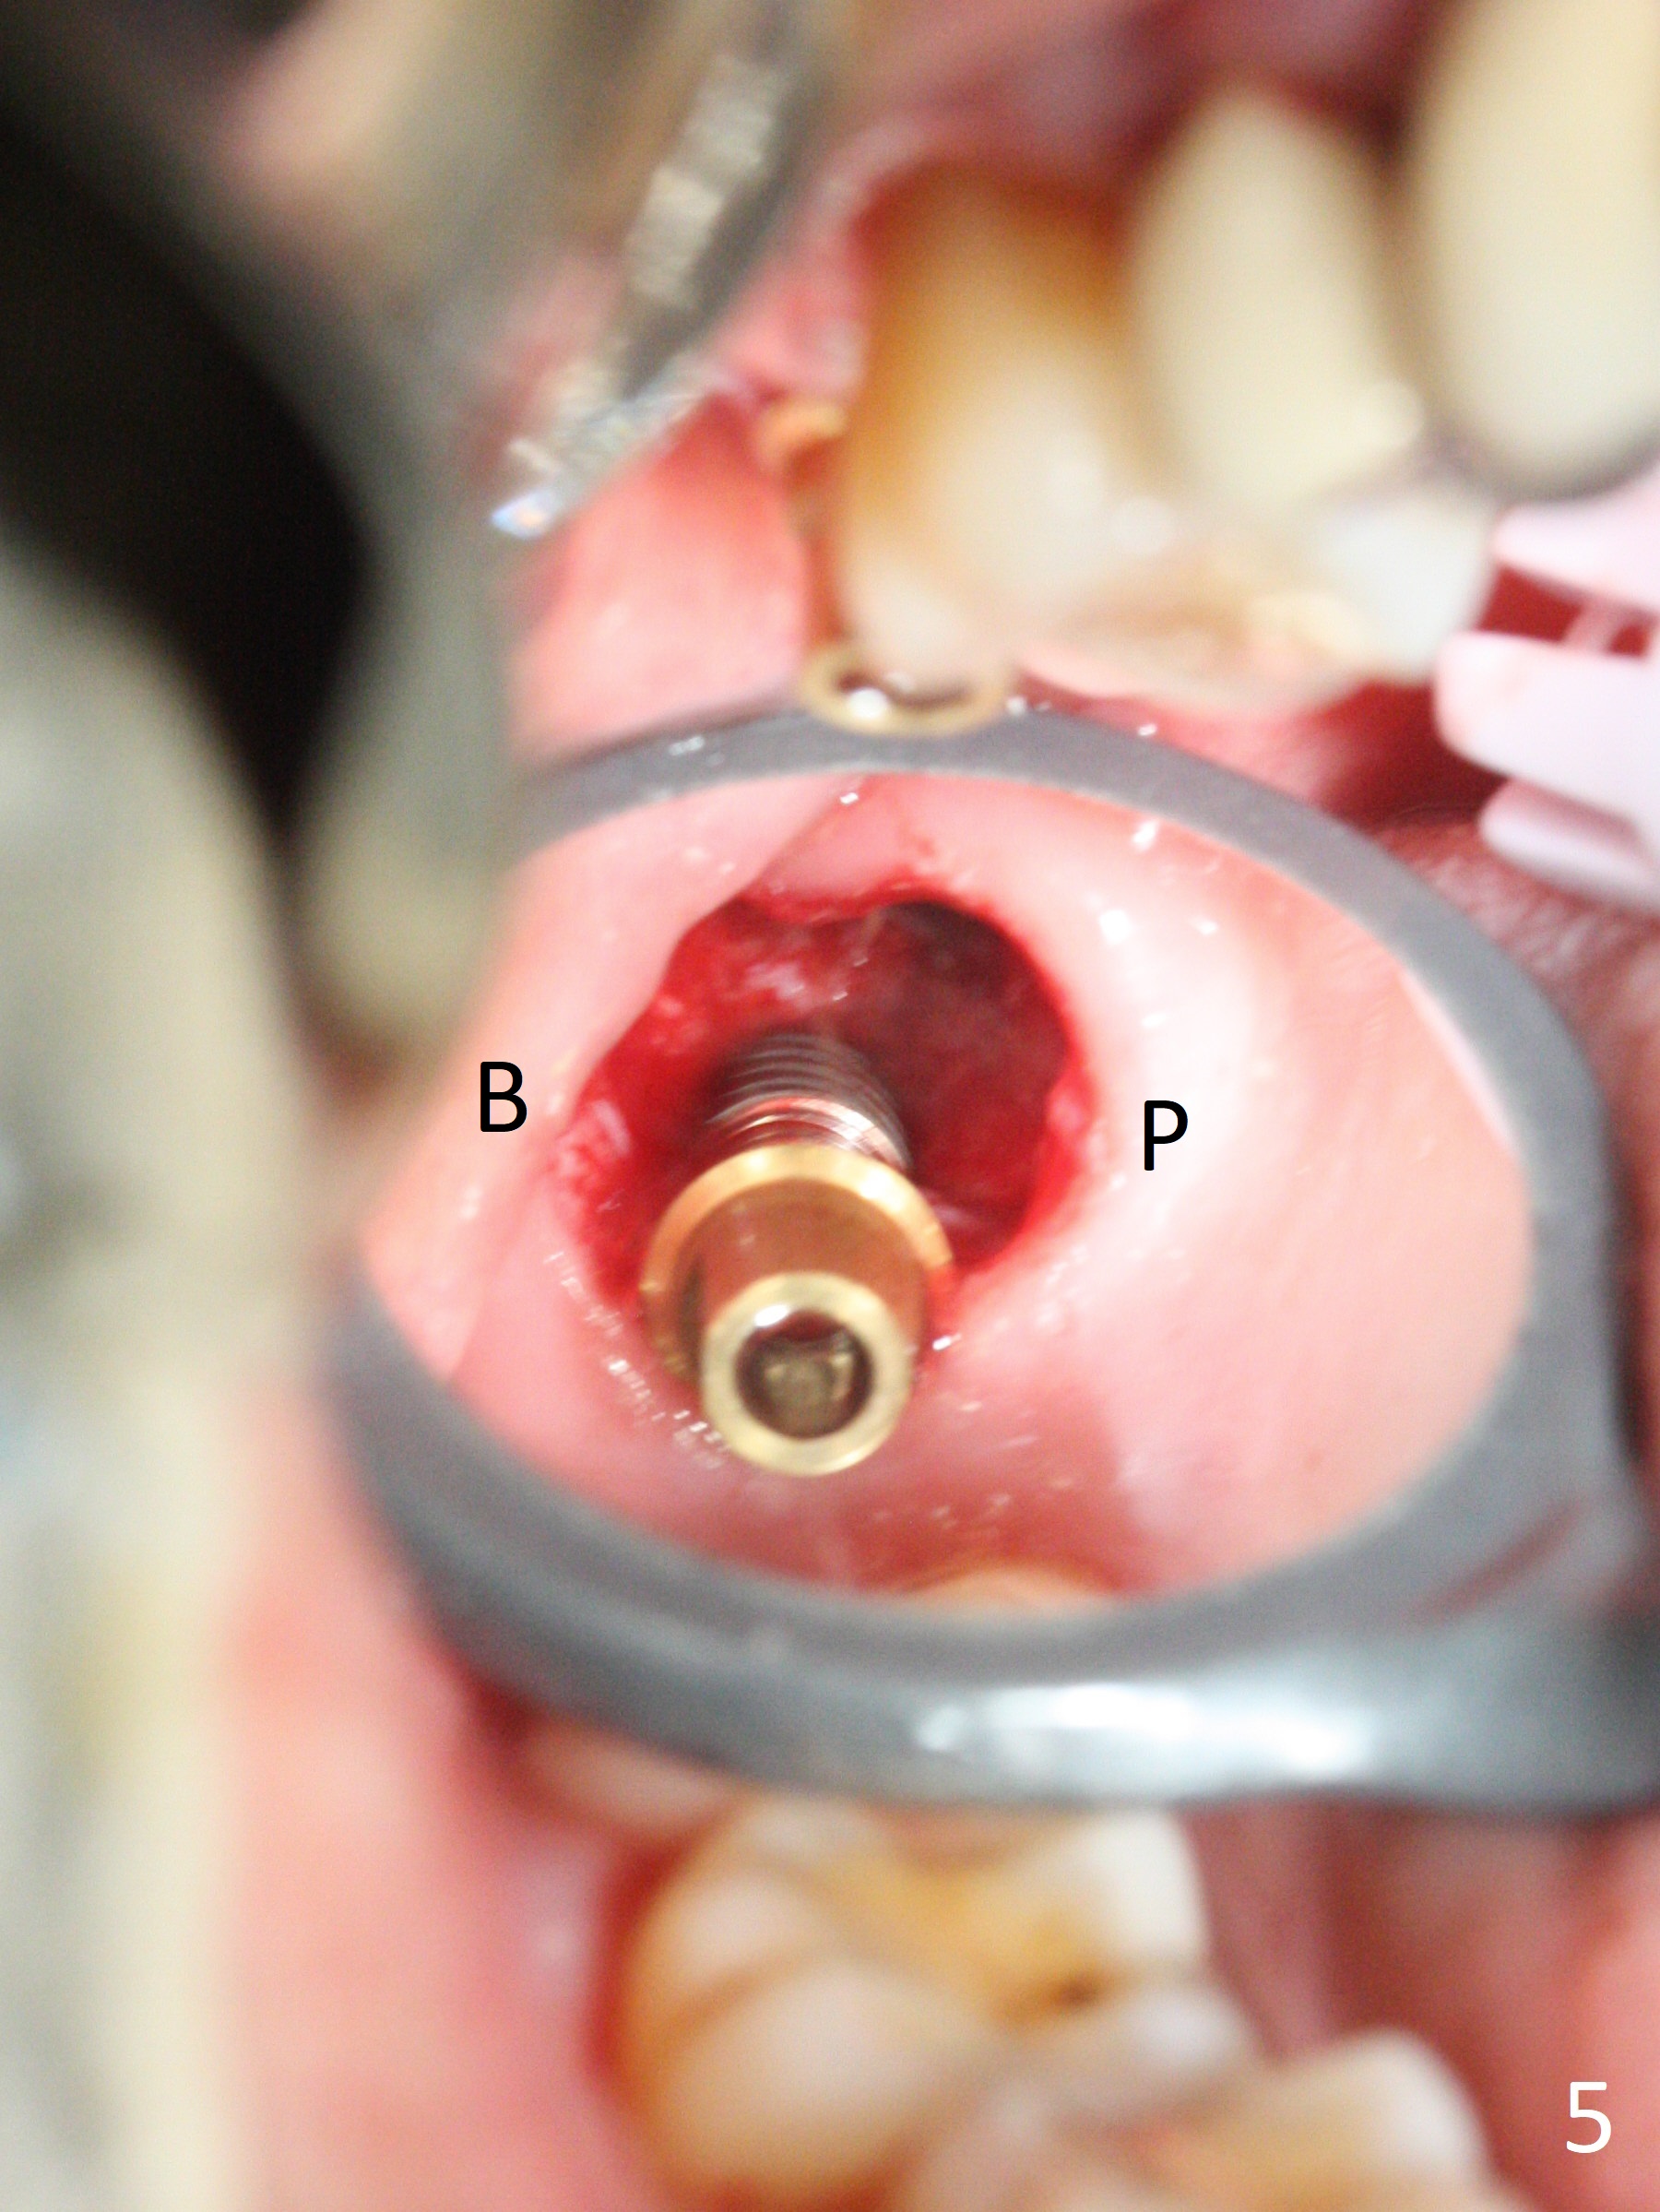

After extraction of the 3rd molar with mesial periodontal defect, osteotomy for 2nd molar implant is initiated in the mesial slope of the 3rd molar socket (Fig.1 red dashed line). When osteotomy is finished with IS drills and sinus lift with Magic Sinus Lifter (S-reamer with 11 mm stopper being short), a 4x10 mm dummy implant is placed with ~ 4 implant thread exposure (Fig.3). Following use of Lindamann bur to move osteotomy mesial and larger drill, a 4.5x10 mm implant is placed with 5-7 implant threads exposed distally (Fig.4,7 (~ 50 Ncm)). The bucco(B)-palatal(P) extent of the implant thread exposure is larger (Fig.5) than that associated with the 4 mm dummy implant (data not shown). The exposed implant surface is covered with Vera Graft (Fig.7*), Collagen plug and an immediate provisional after adjustment of abutment height (Fig.6,7). The bone density distal to the implant is low 3 months postop (Fig.8,9 CBCT) and 3.5 months postop (Fig.10,11). The permanent crown is cemented nearly 4 months postop. The distal cortical bone contacts the implant (Fig.12 ^), while the mesial bone increases in density (*) 2 years postop.